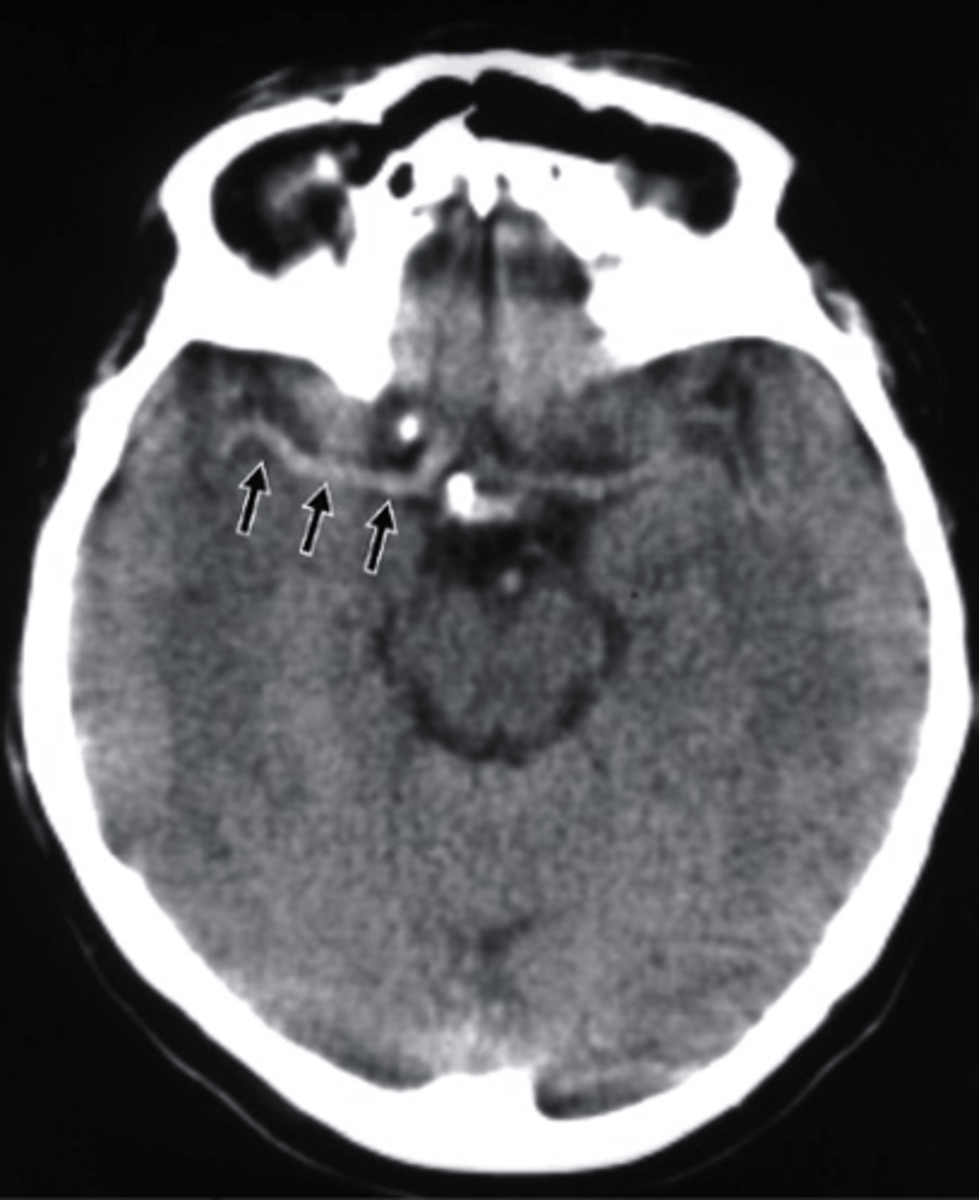

what type of imaging is this?

a. CT scan

b. MRI with IV contrast

c. PET scan

d. Bone Scan